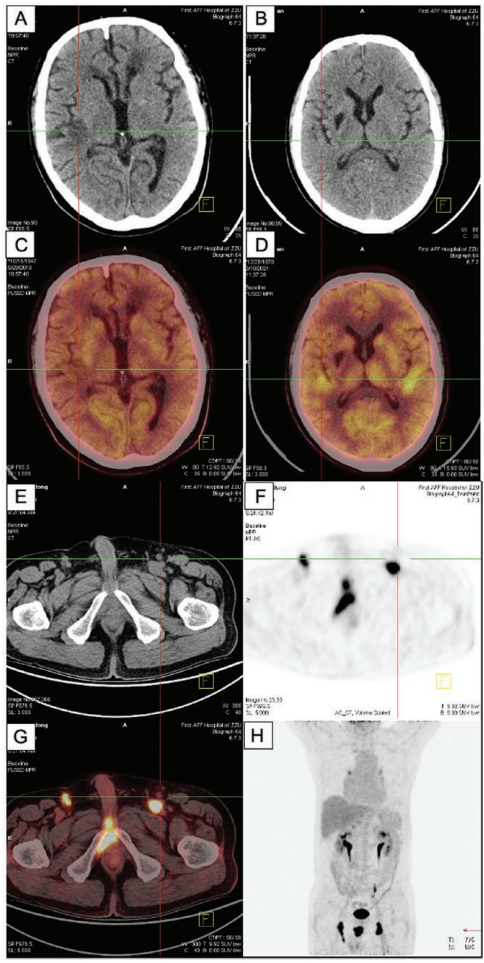

郑州大学第一附属医院肿瘤科张明智教授团队在《The Oncologist》发表的这项开创性研究,首次系统描绘了中国人群IVLBCL的完整临床图谱。通过对2018-2024年间20例确诊患者的全面分析,研究团队不仅揭示了令人惊讶的器官受累新规律,更建立了具有临床实操价值的预后评估体系。这项历时六年的研究采用多维度研究方法:通过18FDG-PET/CT和MRI进行全身病灶评估,采用国际预后指数(IPI)和ECOG评分系统量化疾病状态,运用免疫组化检测CD20/CD5/MUM1等标志物,并通过Kaplan-Meier曲线和Cox回归模型进行生存分析。

研究显示IVLBCL患者平均年龄62.8岁,男女比例11:9,所有病例均为Ann Arbor IV期且IPI≥4分。最具颠覆性的发现是肾上腺成为最常受累器官(45%),远超传统认知的皮肤(20%)和CNS(30%)。PET-CT图像清晰显示双侧肾上腺呈"软组织肿块伴放射性浓聚",SUVmax高达18.8。